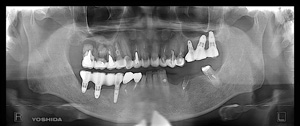

T.S‚³‚ñ 50Î —«@‰ïŽÐˆõ@Žèp“ú  ‚Q‚O‚P‚O”N ‚WŒŽ‚Q‚O“úi‹àj  ãŠ{ : All on ‚U @‰ºŠ{ : All on ‚T@ ƒm[ƒxƒ‹ƒKƒCƒhŽg—p Ö¬“à’ÁÖ@•¹—p@

@@ãŠ{@All on ‚U@’x‰„‰×d

@@@  @@@@@@”‚P‚U@Nb Speedy Shorty Groovy Rp @@ @    ”‚P‚S Rpl  Tapered Groovy Rp ~ ‚W mm@@@@”‚P‚Q Rpl  Tapered Groovy Np ~ ‚W mm

@@@@ @@@@@ ”‚Q‚Q@Rpl  Tapered Groovy Np  ~ ‚W mm@@ ”‚Q‚S Rpl  Tapered Groovy Np  ~ ‚W mm@@@  ”‚Q‚U Nb Speedy Shorty Groovy Rp

@@‰ºŠ{@All on ‚T   ’x‰„‰×d

@@@  @@@@@@”‚R‚U@Bmk MK‡V Rp ‚RD‚V‚T ~ ‚W mm             ”‚R‚S Rpl  Tapered Groovy Rp ~ ‚W mm@@@  @”‚R‚Q Bmk MK‡V Rp ‚RD‚V‚T ~ ‚P‚R mm

@@@@ @@@@@ ”‚S‚Q@Bmk MK‡V Rp ‚RD‚V‚T ~ ‚P‚R mm@@       ”‚S‚S Rpl  Tapered Groovy Np  ~ ‚P‚O mm@@@

@@@@@@ –㉺Š{‹¤‚h‚oƒCƒ“ƒvƒ‰ƒ“ƒg(‚S–{)–„“ü@ƒvƒƒr‘¦“ú‘•’…